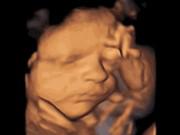

Gần đây, đoạn video ghi lại vẻ mặt của một em bé sơ sinh khi vừa được lấy ra khỏi bụng mẹ đã gây "bão" trên mạng xã hội. Lần đầu nhìn thấy thế giới đầy lạ lẫm, bé mở to đôi mắt nhìn ngang nhìn dọc với vẻ mặt ngơ ngác và có phần hoang mang. Bé còn dùng một tay che bớt phần mặt như đang xấu hổ vì quá nhiều người nhìn vào mình và cười nói.

Vẻ mặt hoang mang của bé khi chào đời cực đáng yêu.